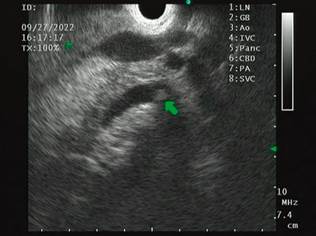

We present the case of a 32-year-old female patient with a history of gastric bypass surgery for morbid obesity. After the associated weight loss, the patient had an episode of abdominal pain with an ultrasound diagnosis of cholelithiasis, which required a laparoscopic cholecystectomy one year before the current consultation. On admission, the patient reported abdominal pain in the upper quadrants, predominantly on the right, associated with mild jaundice and choluria without acholia. With suspected residual choledocholithiasis, the patient was taken for magnetic resonance cholangiography, which failed to identify the causes of pain associated with jaundice. A biliopancreatic endoscopic ultrasound (EUS) was requested, which showed a bile duct of standard diameter with an oval echogenic image of 3.8 mm in diameter, floating and with acoustic shadowing upon the alpha maneuver from the first scanning station (the other stations were not evaluable due to the history of bypass; Figure 1). This finding is compatible with choledocholithiasis, for which ERCP is indicated.